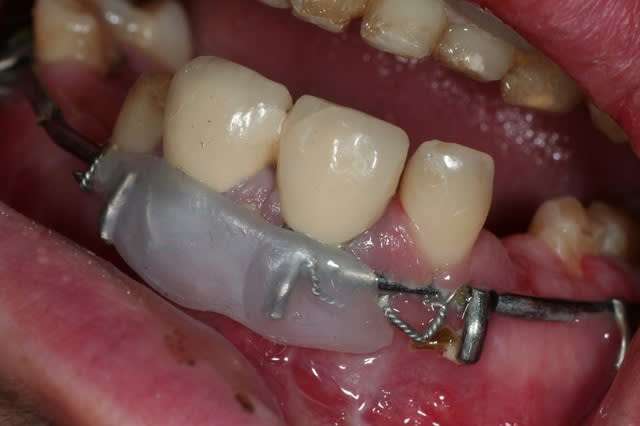

pas le temps de faire des commentaires ce matin, je balance le cas, et lâchez vous

donc, effectivement, un gros choc avec fractures multiples. effectivement marco, c'est un cas long mais qui n'a rien de sorcier en soi, je l'ai posté parce qu'il étendu et impressionnant.

ce cas n'est pas encore réalisé, je vous le livre brut de décoffrage, et j'espère le mener à bout et partager les différentes étapes sur le site.

je n'ai rien entrepris pour l'instant parce que l'ouverture buccale est très limitée, et je voudrais que le maxillo débarrasse le patient de toute la ferraille avant de commencer.

pour l'instant j'en suis à concevoir une approche, et je bute sur 36 et 37: endo + élongation + ccm, ou alors extraction? je crois que la 36 va sauter, mais 37 m'embête.

autre chose qui m'embête, c'est d'être obligé d'attendre la dépose des mini-plaques avant de pouvoir implanter 23 , 24 et 13.